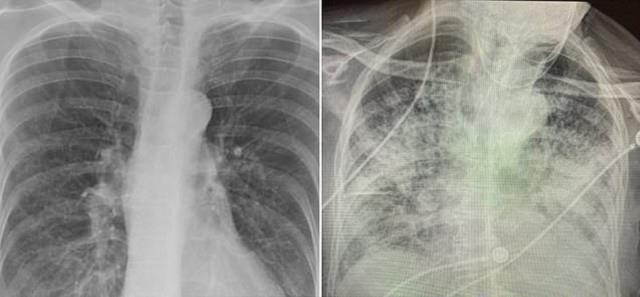

Soldaki görselde sigara içen bir bireyin akciğer filmi görülürken sağda ise koronavirüsü yenmiş bir bireyinki yer alıyor.

Soldaki görselde sigara içen bir bireyin akciğer filmi görülürken sağda ise koronavirüsü yenmiş bir bireyinki yer alıyor.Akciğer filminde siyahlar ne kadar fazlaysa o kişinin ciğer kapasitesi ve sağlığı o kadar iyi anlamına geliyor. Beyazlığın artması akciğerin kapasitesinin azaldığı anlamına geliyor.

Röntgen sonuçlarında koronavirüs geçirmiş ve sağlığına kavuşmuş kişilerin ciğerlerindeki hasarın sigara tiryakilerinden çok ama çok daha kötü olduğunu gösteren Bankhead-Kendall, "Sağlıklı bir bireyin röntgen sonucunda siyah alan büyük olur. Bu da o kişinin ciğerlerine alabileceği oksijen seviyesini gösterir. Sigara içenlerde hafif hareler yer alırken koronavirüs hastalarının ciğerleri ise bembeyazdır. Yani bu da koronavirüsü yenenlerde bile akciğer sorunları yaşanabildiğini gösteriyor" dedi.